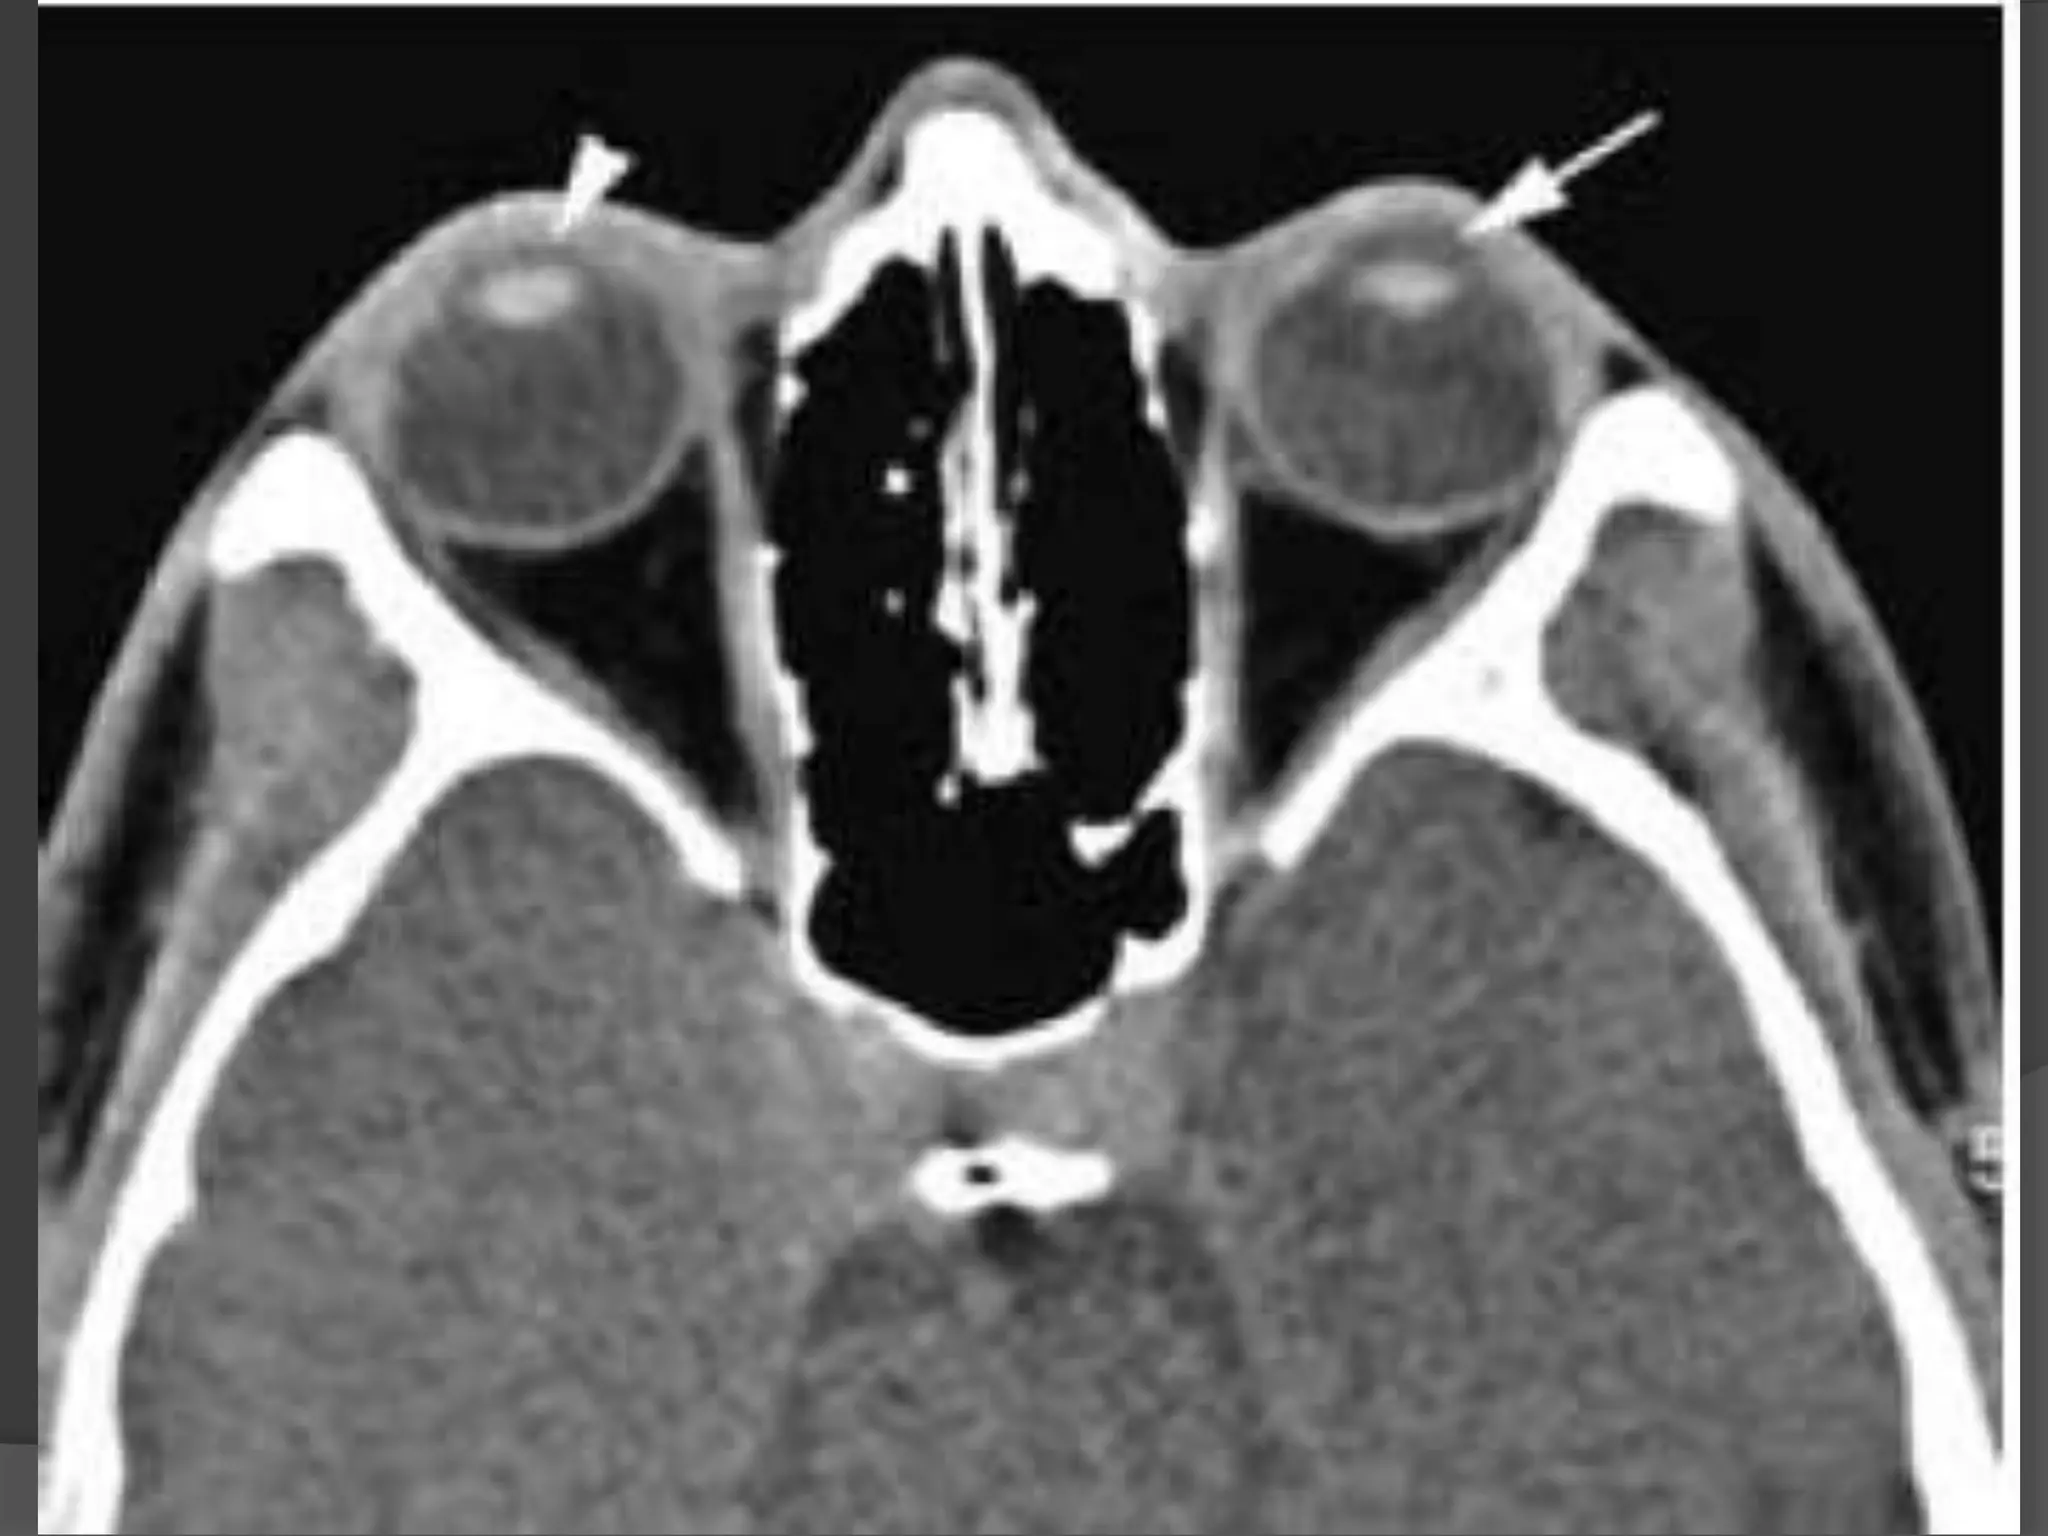

Imaging : MRI is the modality of choice with hyper intense signal of

T2WI due to fluid and edema. Fat Sat contrast enhanced T1WI will show

areas of demyelination. CT relatively insensitive.

Straightening and thickening

of right optic nerve.

Optic Neuritis. CE Fat Sat T1W axial

(B) MR images demonstrate subtle enlargement and enhancement of the left

optic nerve (curved arrow).

T 2 WI (C) demonstrates corresponding increased signal intensity (straight

arrow).